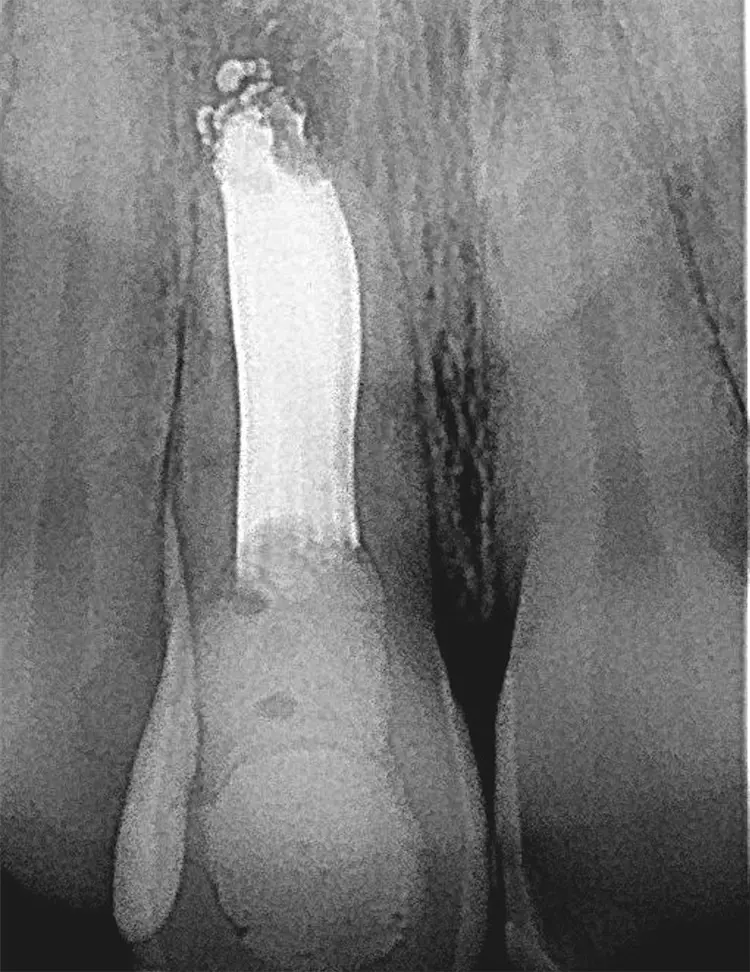

Auffällig war der Taschenbefund mit 9 mm bukkal und palatinal an Zahn 11, der auf eine Längsfraktur hindeutete. Im Rahmen der radiologischen Diagnostik wurde ein Orthopanthomogramm (Abb. 1) und ein Zahnfilm regio 11 (Abb. 2) erstellt mit sichtbarer periapikaler Aufhellung regio 11.

Zahnklinik Bochum